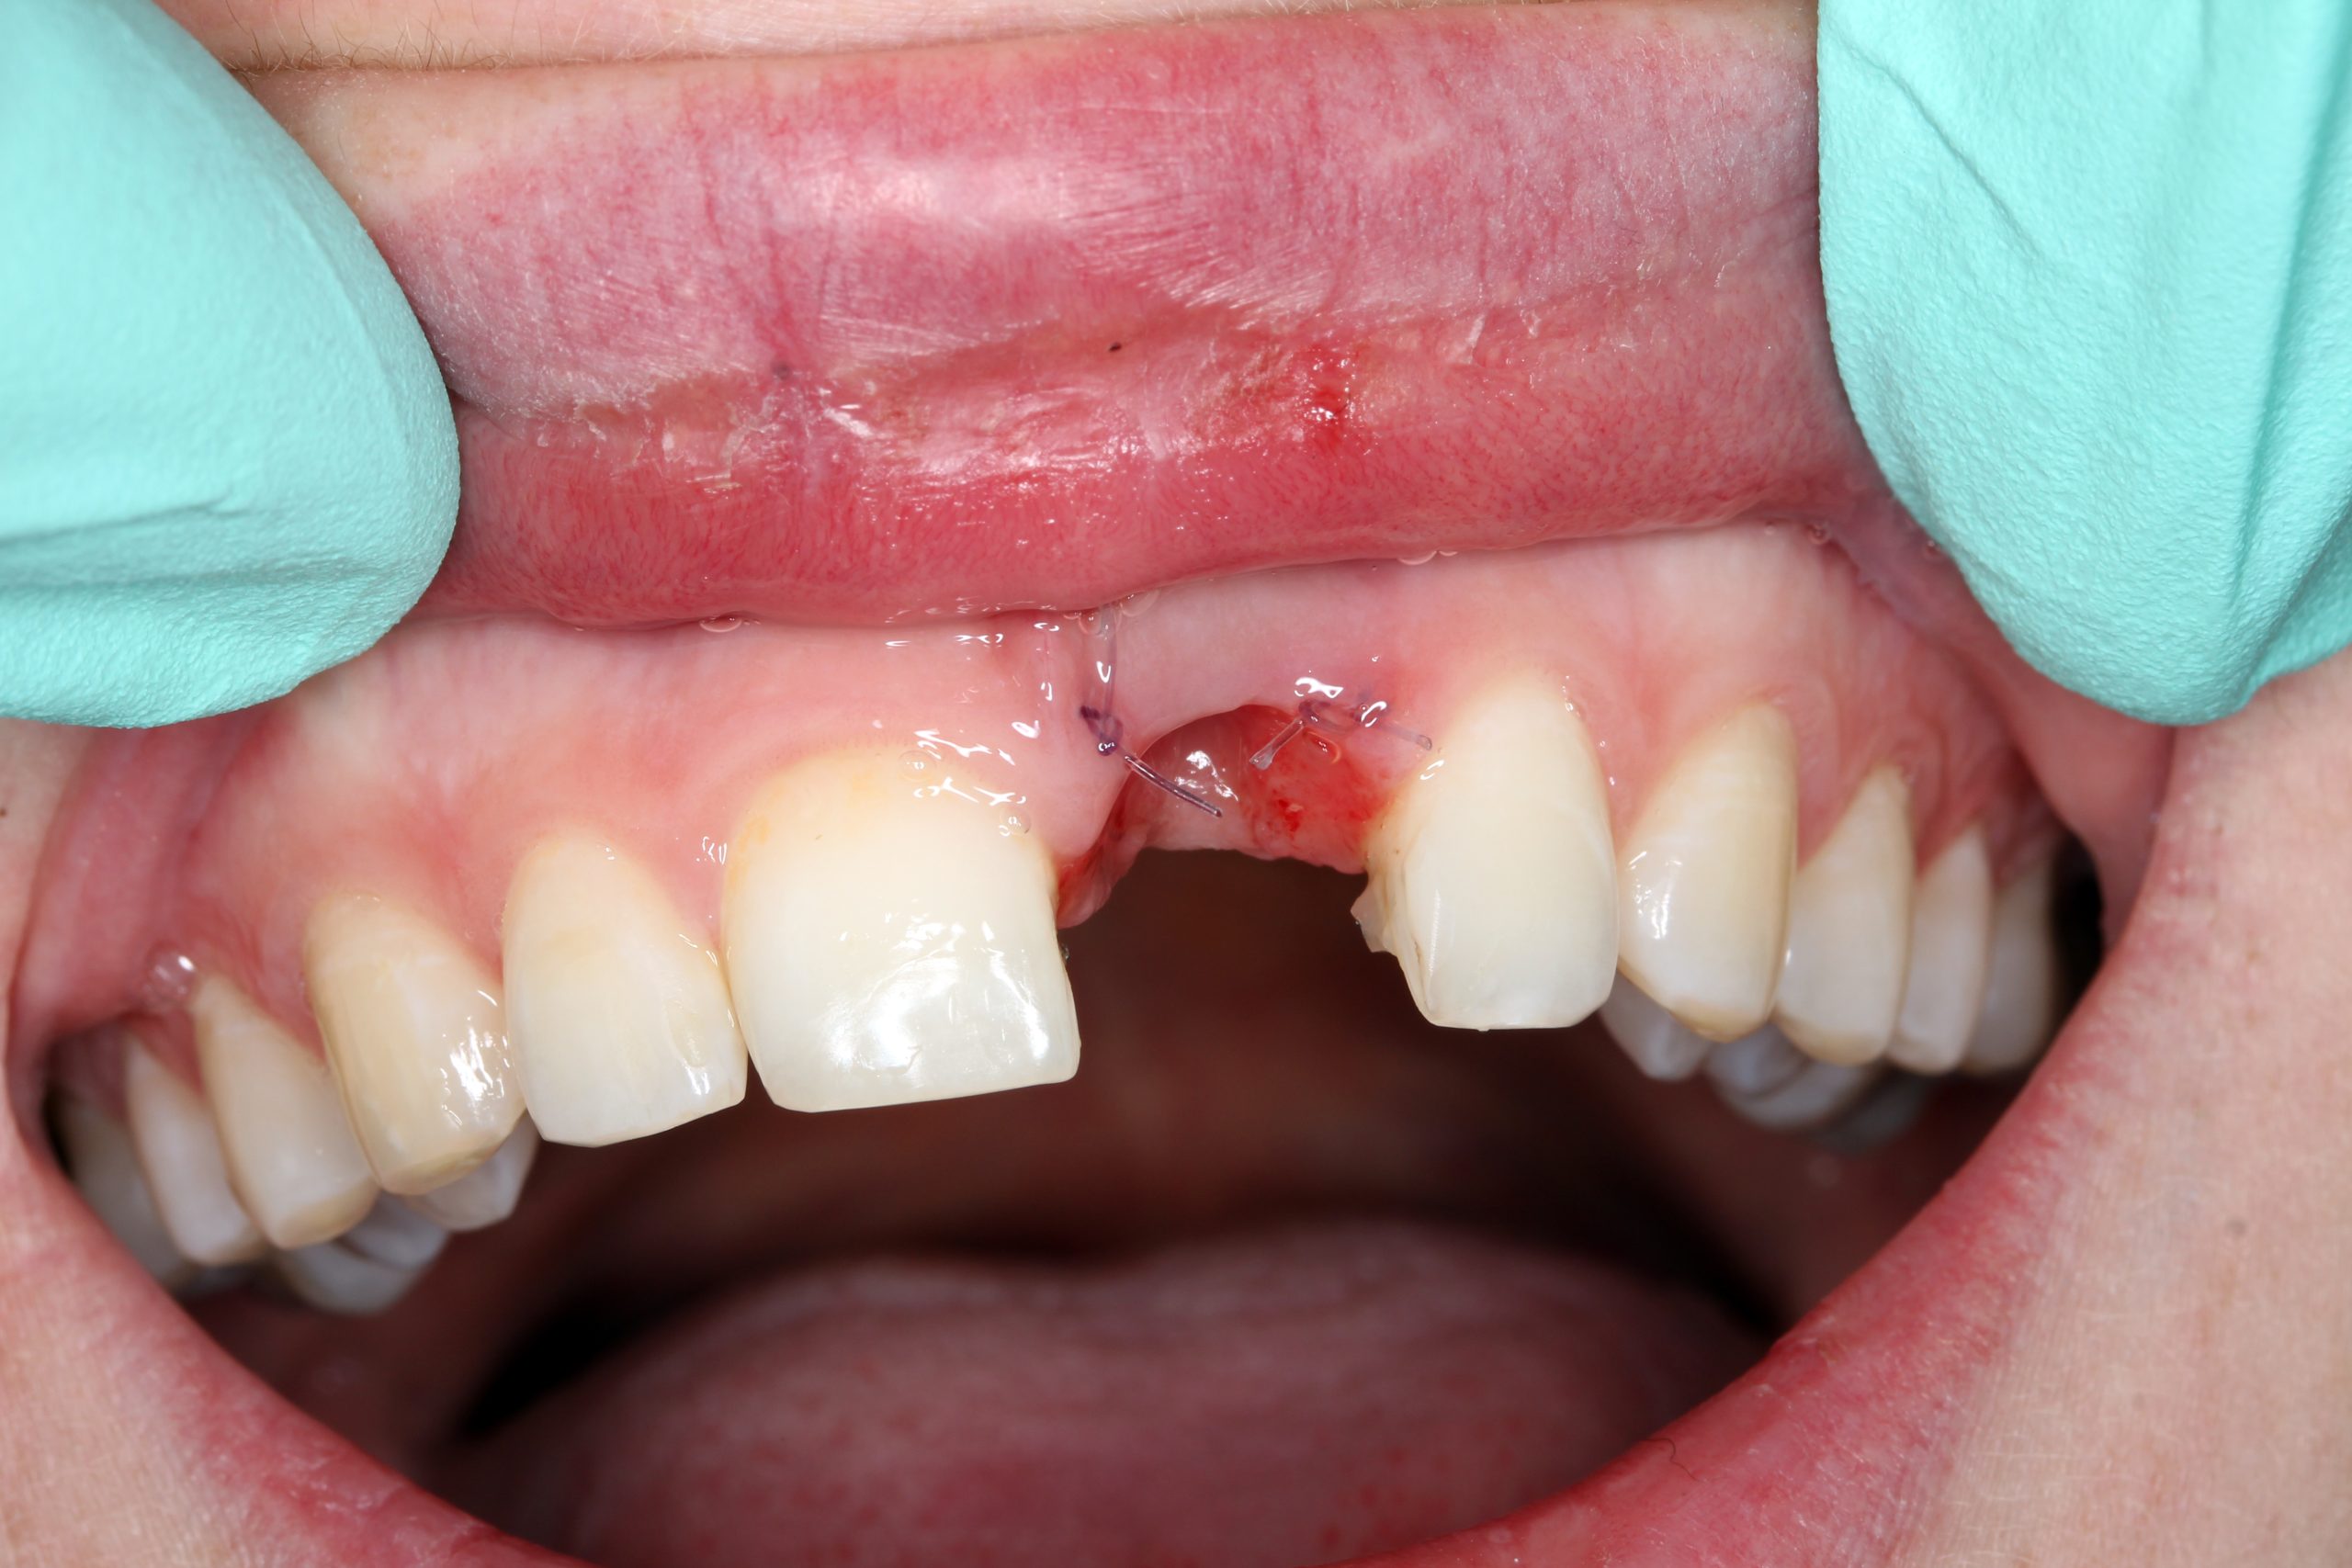

Nach dem Entfernen der Krone: eine perfekt epithelisierte Extraktionswunde und erhaltene Interdentalpapillen. Die Drahtschiene, mit der die Zahnkrone zeitweilig fixiert worden war, wurde als Kontrollelement für das Einsetzen des Implantats vorübergehend zurückbehalten.

Der Mukoperiostlappen wurde palatinal angehoben und teilweise vestibulär mobilisiert. Ein 14 mm langes Implantat BioniQ® von LASAK mit Ø 4 mm wurde eingesetzt und nach dem Entfernen des Trägers ein provisorischer Aufbaupfosten befestigt.